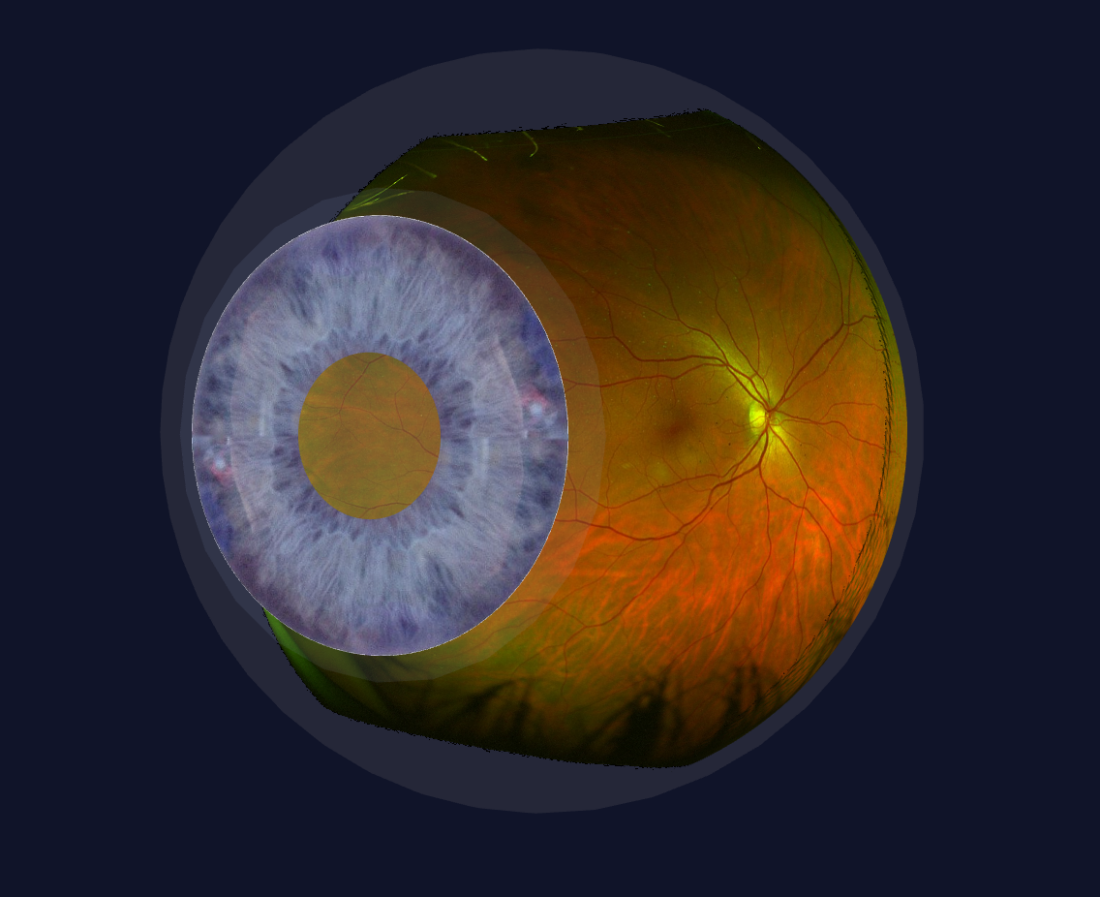

Die Augen Vorsorge Untersuchung heisst bei uns „Panorama Check“, weil unter anderem mit einer Ultra-Weitwinkel Kamera die Netzhaut abgebildet wird. Dazu wird das Auge sorgfältig von vorne bis hinten angeschaut. Besonderer Fokus wird gelegt auf die Netzhaut mit dem Sehnerv und der Makula, aber auch die Augenlinse, die Vorderkammer, die für die Regulierung des Augendruckes wichtig ist. In der heutigen Zeit mit intensiver Bildschirmnutzung wird aber auch der Tränenfilm, die Schleimhaut und die Hornhaut kurz angeschaut. Zudem erfolgen Funktionsteste, um gröbere Auffälligkeiten in der Augenbeweglichkeit oder Pupillenreaktion festzustellen.

Der Augendruck ist also nur eines der Puzzleteile. Nachfolgend sehen Sie Aufnahmen wie sie bei uns im Rahmen eines „Panorama Check“ entstehen.